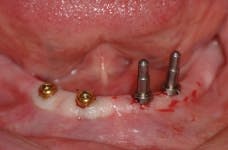

All-on-4 advocates claim that this type of treatment plan reduces cost and saves treatment time, but with the introduction of the ScrewIndirect one-piece implant that provides the implant, abutment, comfort cap, and transfer at a fraction of the cost of the implant alone from all the major implant companies, the economics argument for using the minimum number of implants is no longer valid. The ScrewIndirect screw-receiving platform allows splinting of implants that have up to 40 degree divergence, allowing distal angulations of up to 20 degrees if desired. Placement of five implants in the lower symphysis and six anterior to the maxillary sinuses can be relatively straight and still support adequate length of distal cantilevers. Four ScrewIndirect implants can also be placed, as shown below, splinted with a distal attachment for retention of an overdenture, but providing the patient with a fixed-detachable prosthesis that eliminates the need for a removable prosthesis is a more natural solution to restoring an edentulous jaw.

The ScrewIndirect one-piece implant offers a 3.0 mm D implant with adequate strength. All four diameter options (3.0 mm, 3.7 mm, 4.7 mm and 5.7 mm) have the same 5 mm D multi-unit platform. The 3.0 mm D implant allows treatment of narrow ridges and simplifies accurate placement during flapless surgery. Providing teeth in one day to edentulous patients and immediate implant placement following extractions is becoming the treatment of choice. The patient's existing denture is converted to a fixed-detachable prosthesis immediately following implant placement. This is accomplished by attaching titanium sleeves to the implants that project through holes cut in the denture and attached them to the denture with cold-cure acrylic followed by shortening the denture flanges.